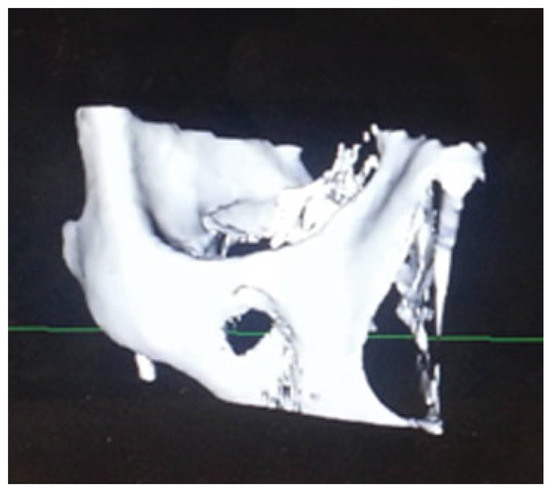

Figure 2.

Coronal section of orbital floor fracture in Case 1.

A 59-year-old female presented to the maxillofacial outpatient department following a mechanical fall resulting in a left orbital floor fracture. Enophthalmos of 2 mm was present and a CT scan revealed a large floor defect (Figure 2 and Figure 3). Diplopia was present on upward gaze. A rapid prototyping model was fabricated and a Synthes titanium orbital plate was further adapted preoperatively. The orbital floor was accessed via a mid-lid approach and the modified titanium orbital plate was inserted. No further adaptation of the plate was required and the time taken from insertion of the plate to final fixation was less than 1 minute, as no further adaptation was necessary. Position was confirmed with an intraoperative CT scan (O-arm, Medtronic [Medtronic, Minneapolis, MN]) (Figure 4, Figure 5 and Figure 6). The patient’s diplopia and enophthalmos had resolved 2 weeks postoperatively and no complications were noted at the 6th week follow-up.